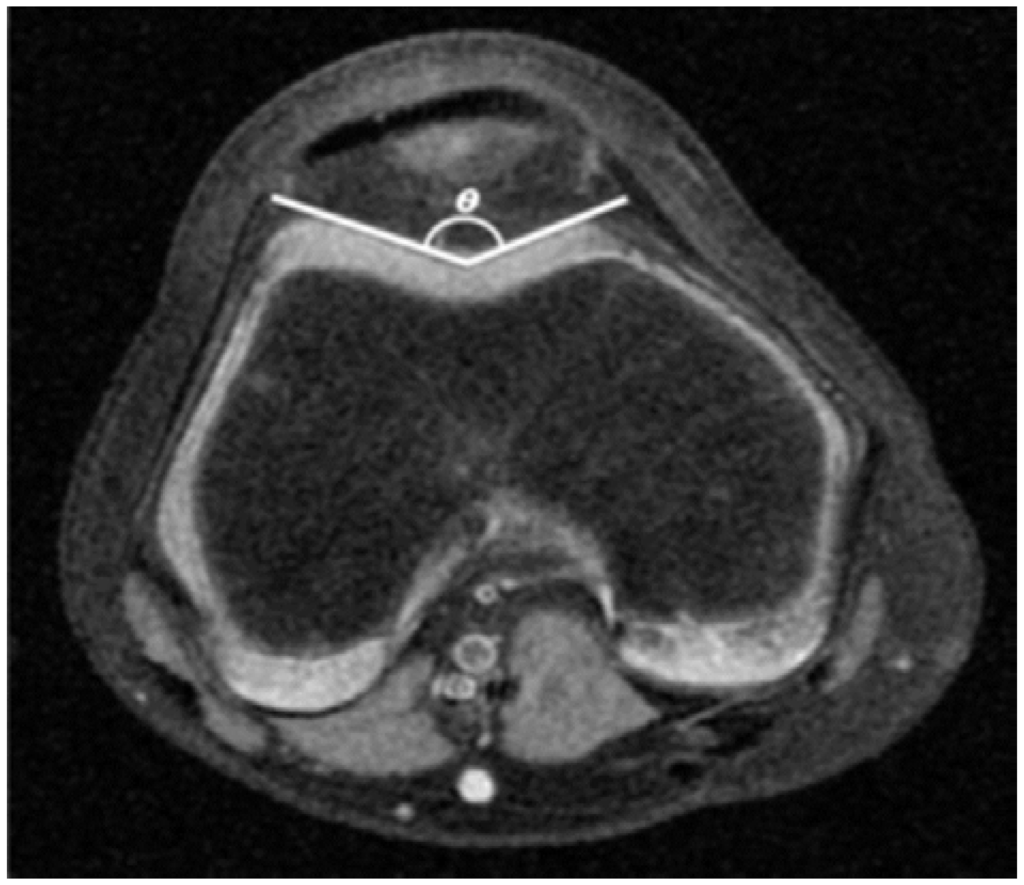

Figure 5.

Sulcus Angle (SA). The angle (θ) between the lateral and medial facet is measured.